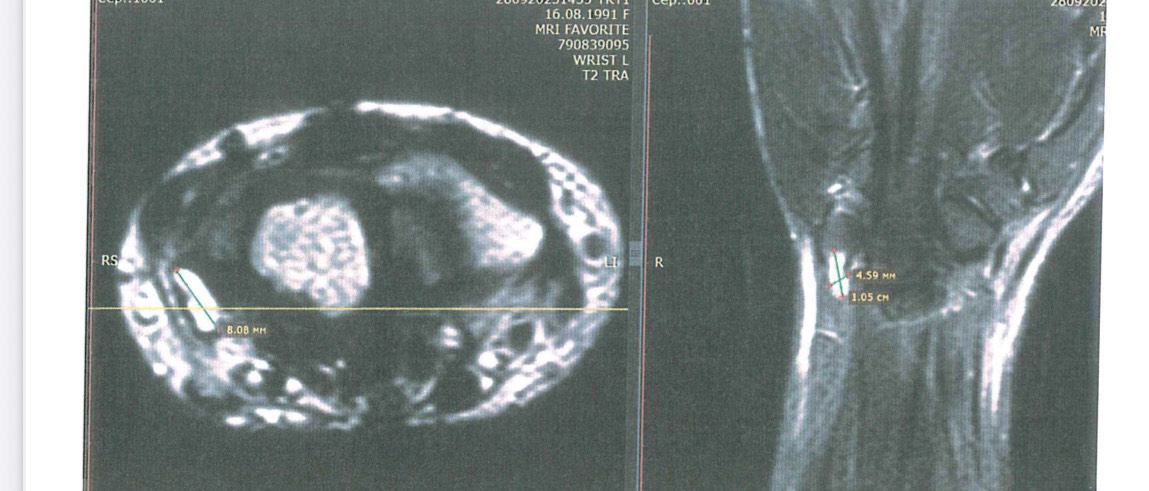

Аны бачча ыксалга киста кисти руки буолбут, слишком много коржей накатала уьу😮💨

Рентген ничего не показал миэхэ эмиэ, просто без изменений диэн написано было.

Кт или мрт учугэйдик кордорор, но кт вредный ди.